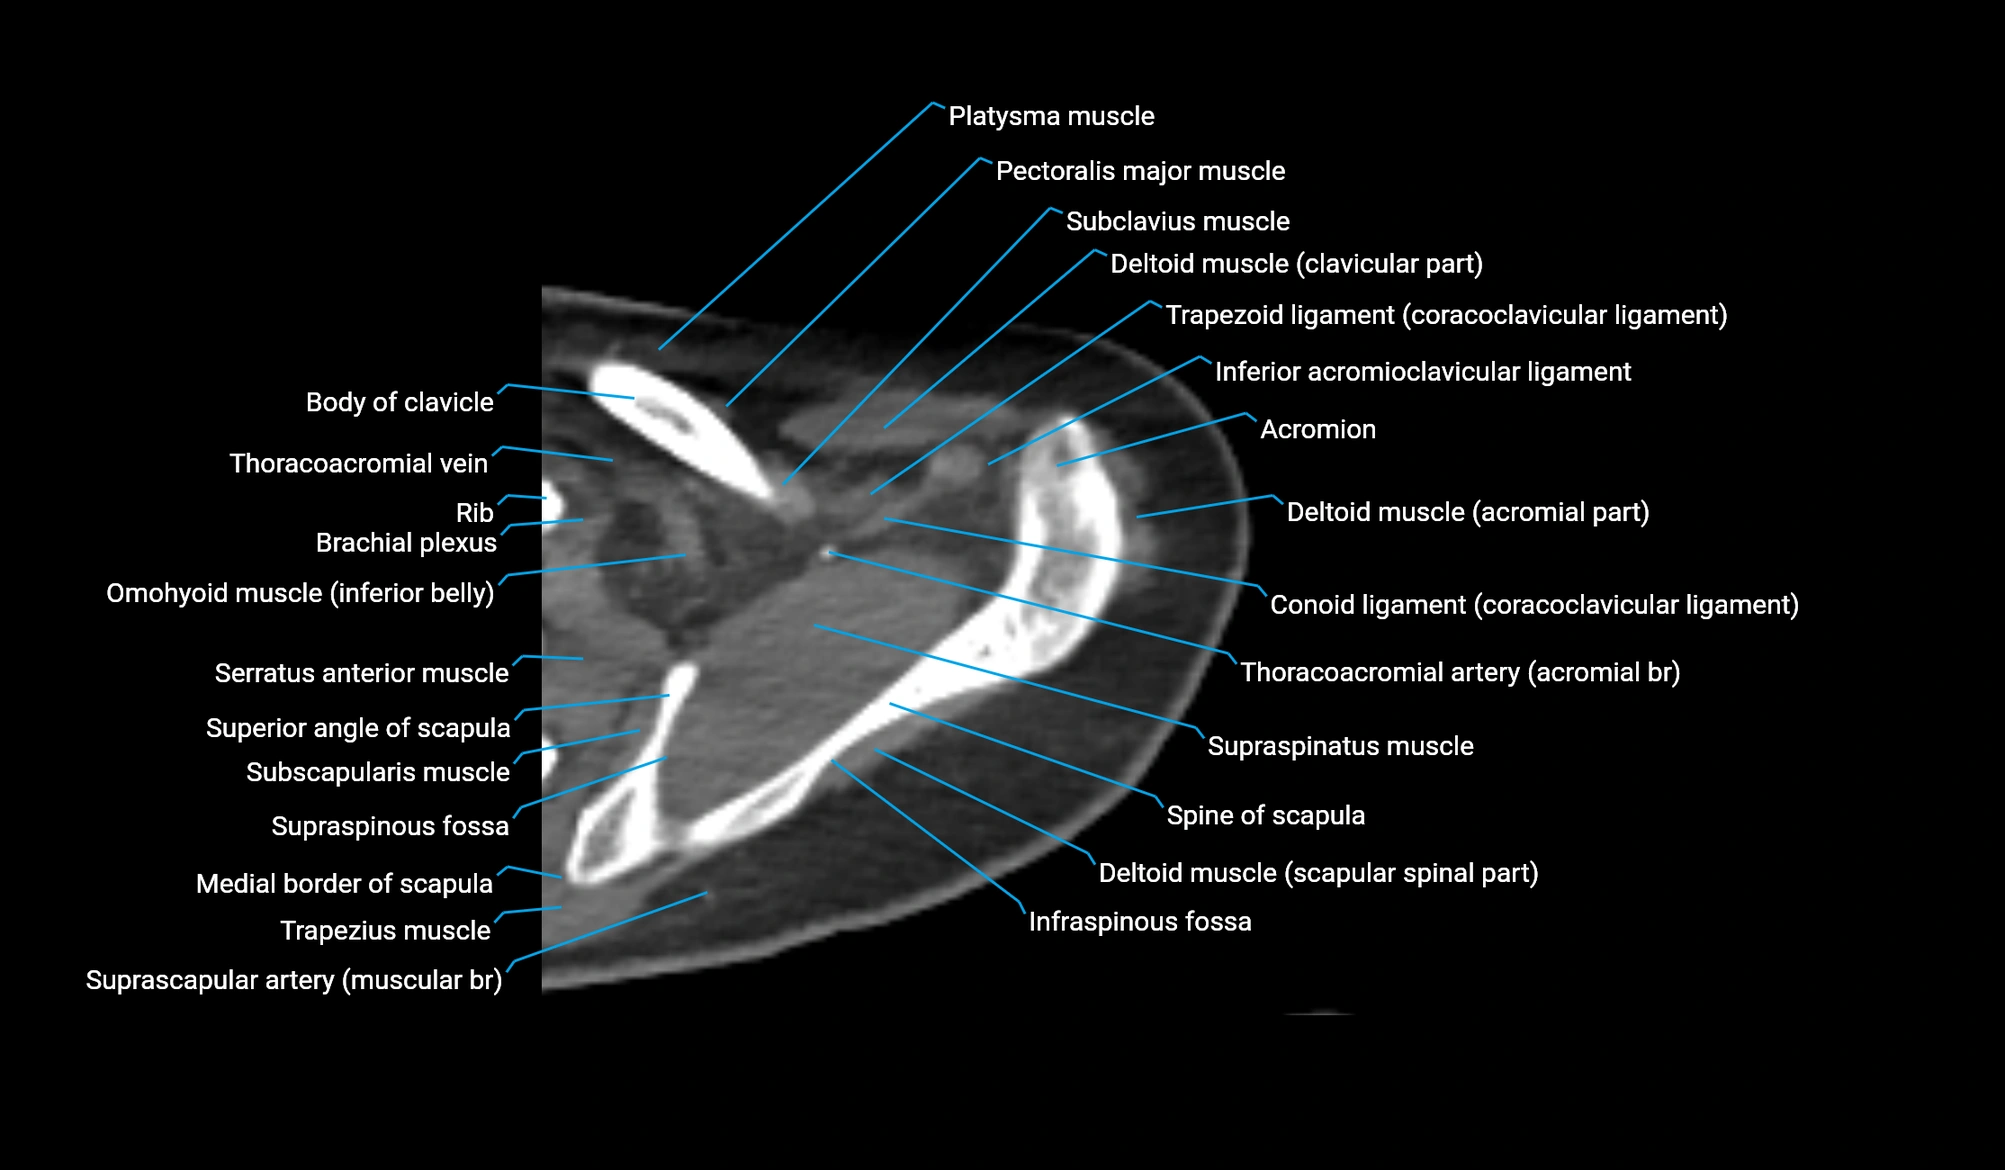

- Clavicular part of deltoid muscle

- Acromial part of deltoid muscle

- Scapular spinal part of deltoid muscle

- Conoid ligament

- Inferior acromioclavicular ligament

- Acromion process of scapula

- Inferior belly of omohyoid muscle

- Brachial plexus

- Pectoralis major muscle

- Subclavius muscle

- Subscapularis muscle

- Supraspinatus muscle

- Spine of scapula

- Infraspinous fossa

- Medial border of scapula

- Superior angle of scapula

- Trapezoid ligament